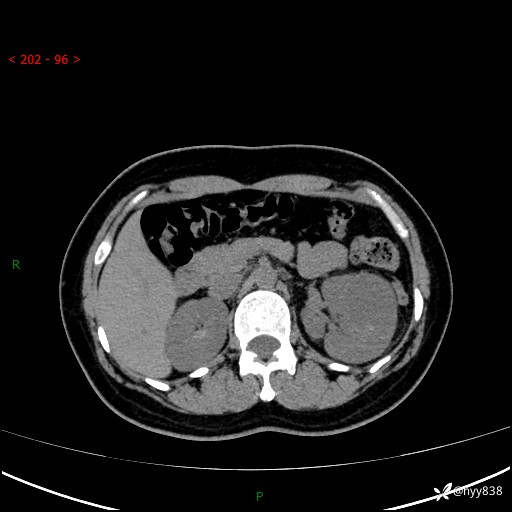

现病史:患者于1周前因左侧腰腹部间断胀痛不适,无恶心呕吐,无明显肉眼血尿,无畏寒发热,无尿频尿急,起病初,患者来我院就诊,查CT提示左肾低密度影,外周血提示:白细胞11.25*10^9/L.行抗感染治疗后未见明显好转,06-18泌尿系增强CT提示左肾类圆形低密度占位(脓肿?肿瘤?),大小:4.0*3.2cm,为求进一步治疗,门诊以“左肾占位”收住我科。 起病以来,患者精神佳,饮食、睡眠良好,大小便正常,体力体重无明显变化。

双肾CT平扫+增强